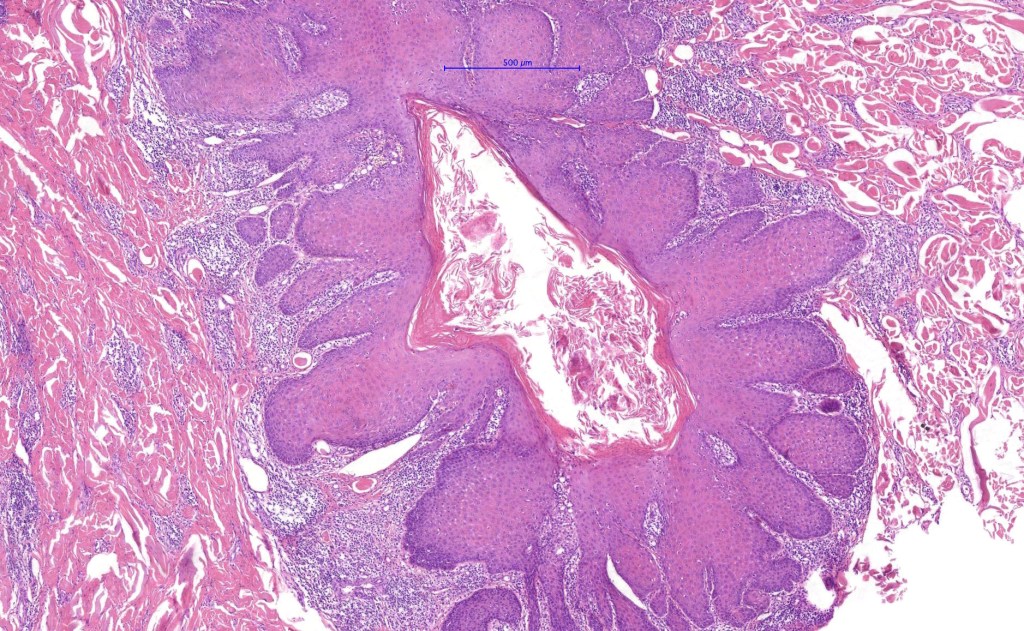

Histological features

•Multilobulated cyst with associated lobules of well differentiated squamous epithelium

•PAS+ve cytoplasmic vacuolation indicating outer root sheath differentiation

•+/- peripheral palisading

•No pleomorphism or significant mitotic activity

•Eosinophilic basement membrane

•Infundibular>trichilemmal keratinization